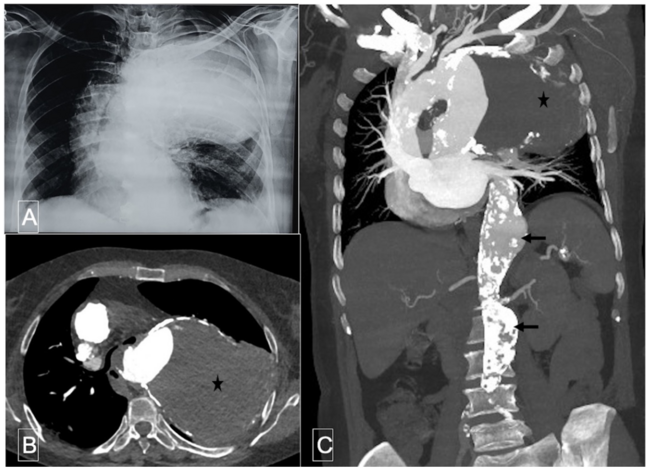

A 61-year-old hypertensive female patient with dyslipidemia presented with hoarseness of voice for the past 2 months. Her physical examination revealed tracheal shift to the right and dullness and decreased breath sounds in the left infrascapular area. Chest radiograph showed a smooth, round opacity in the upper and middle lung fields in the left lung with its broad base toward the upper mediastinum (Figure 1A). Computed tomography (CT) of the chest and aorta revealed a giant saccular aneurysm of the proximal descending thoracic aorta (DTA) with eccentric thrombosis of most of the aneurysmal sac (Figure 1B and Figure 1C). CT aortogram also showed 2 additional aortic aneurysms at the distal DTA and abdominal aorta with extensive background atherosclerotic disease. The patient was advised to consider surgical repair of the aneurysm, but refused surgery and decided to remain on medical therapy.